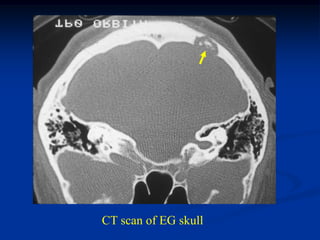

Case #434

x-ray resection specimen

24 year male with EG skull

CT scan of EG skull

Photomic